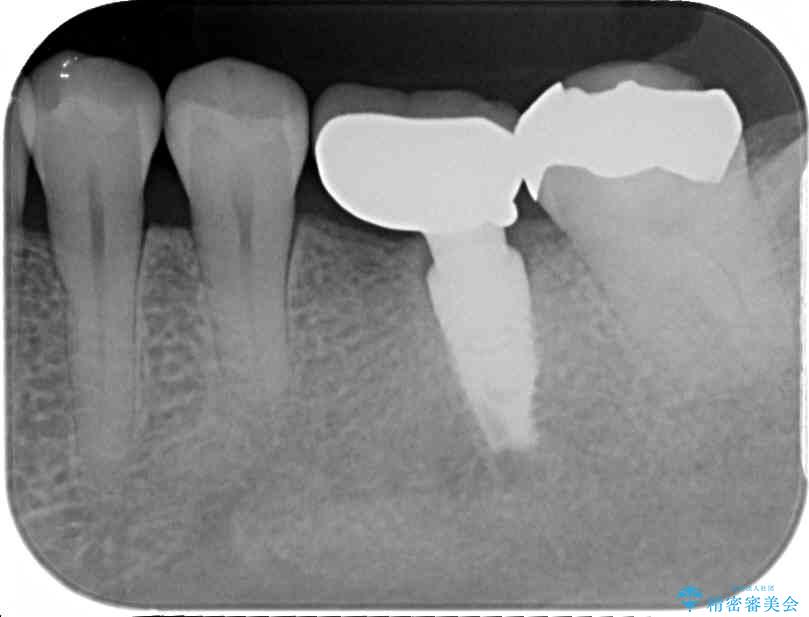

銀歯の装着されている奥歯がしみるとのことで来院された患者様です。

銀歯周辺の歯が欠けており、むし歯も進行している状態であったので、オールセラミッククラウンにて補綴治療を行うこととしました。

• しみる奥歯 オールセラミッククラウンによる補綴治療 治療前画像